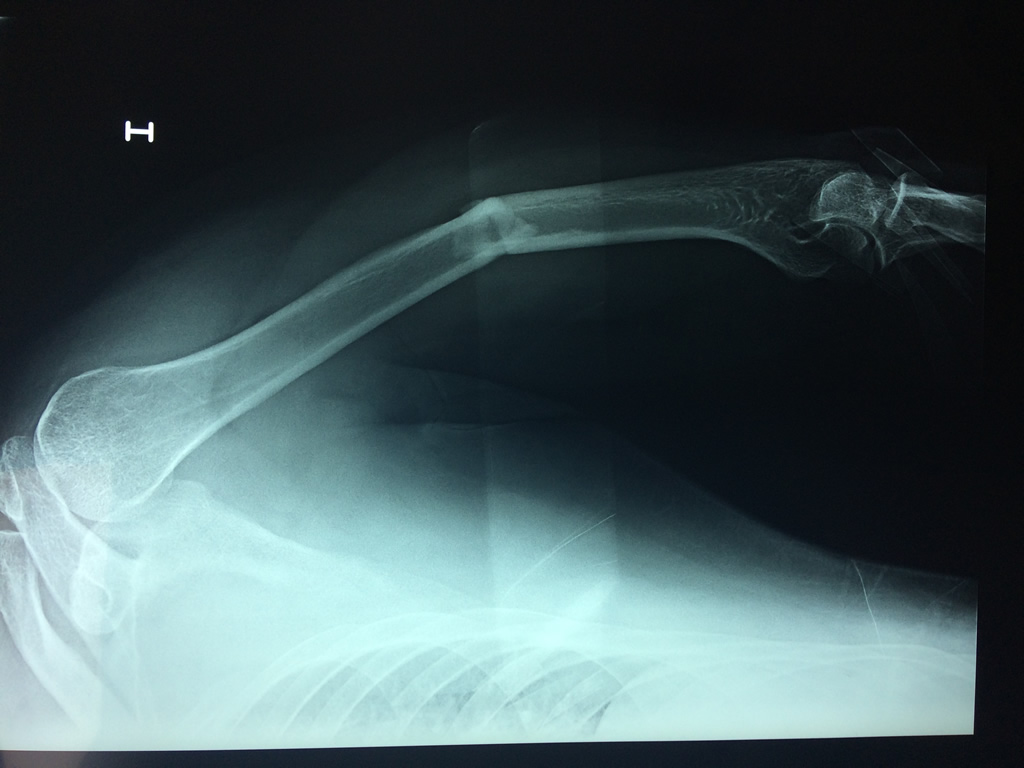

Cirugías de Muñecas

El Húmero (en latín, humerus) es el hueso más largo de las extremidades superiores en el ser humano. Forma parte del esqueleto apendicular superior y está ubicado en la región del brazo. ... El extremo proximal del húmero tiene la cabeza, cuellos quirúrgico y anatómico y tubérculos mayor y menor.